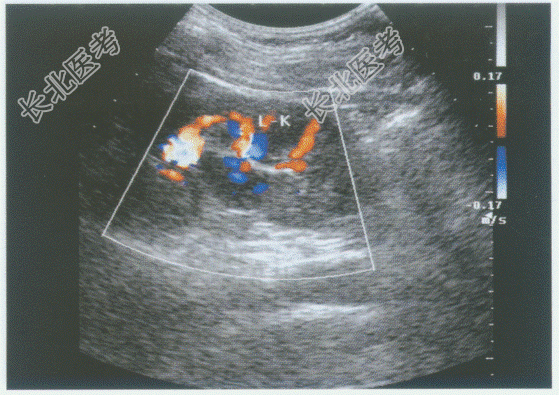

- 单项选择题临床资料:男, 48岁,常规体检。

超声综合描述: 左肾集合系统中部可见2.5cm×1.9cm低回声区,形态不规则, CDFI:内见少许动、静脉血流信号。见下图及彩图。

超声提示:  A、左肾肥大肾柱

B、左肾盂旁囊肿

C、左肾积水

D、左肾集合系统中部实性占位

E、右肾错构瘤